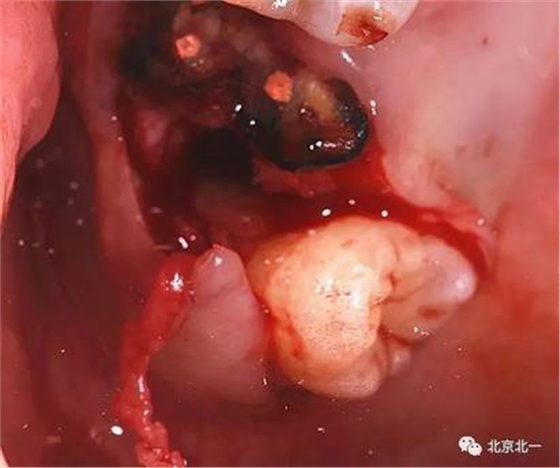

圖六:牙冠完整被挺松。

圖八:一見廬山真面目